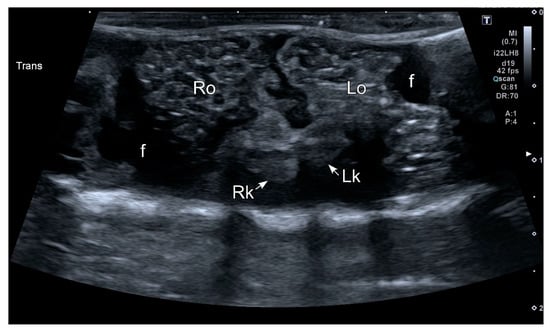

3.2. Ultrasonography